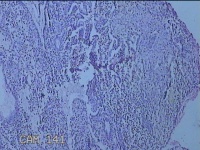

宫腔内容物

性别

女

年龄

47岁

临床诊断

1.异常子宫出血 2.慢性宫颈炎

一般病史

不规则阴道流血21天。

标本名称

大体所见

灰白暗红色不规则碎组织2.5x1.8x0.3cm一堆。

图3